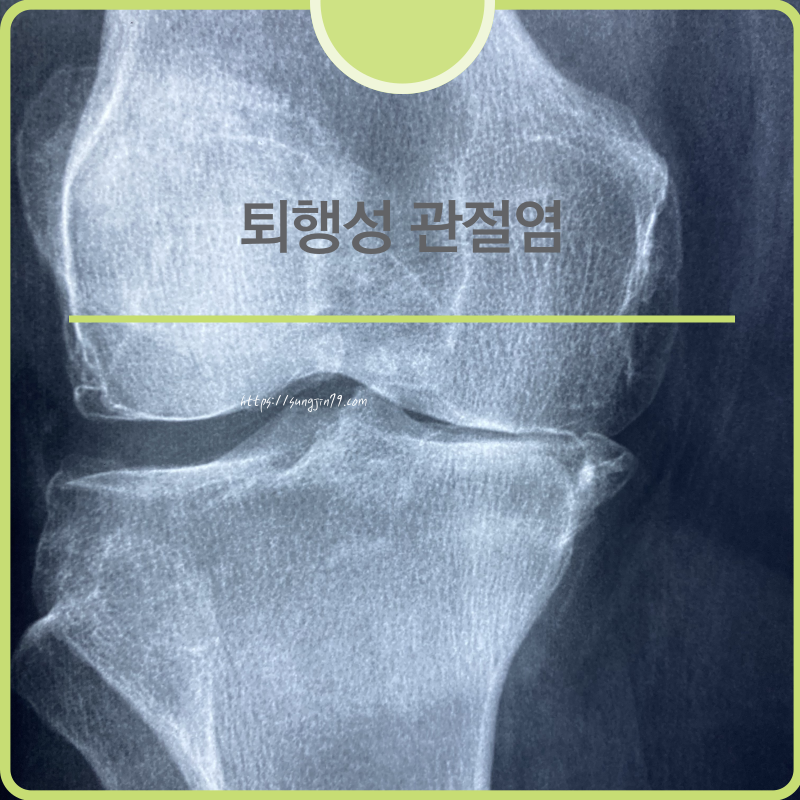

| 🦴 퇴행성 관절염 예방을 위한 생활습관 10가지 (0) | 2025.04.28 |

| 퇴행성 관절염(골관절염) 완벽 가이드 (0) | 2025.04.28 |